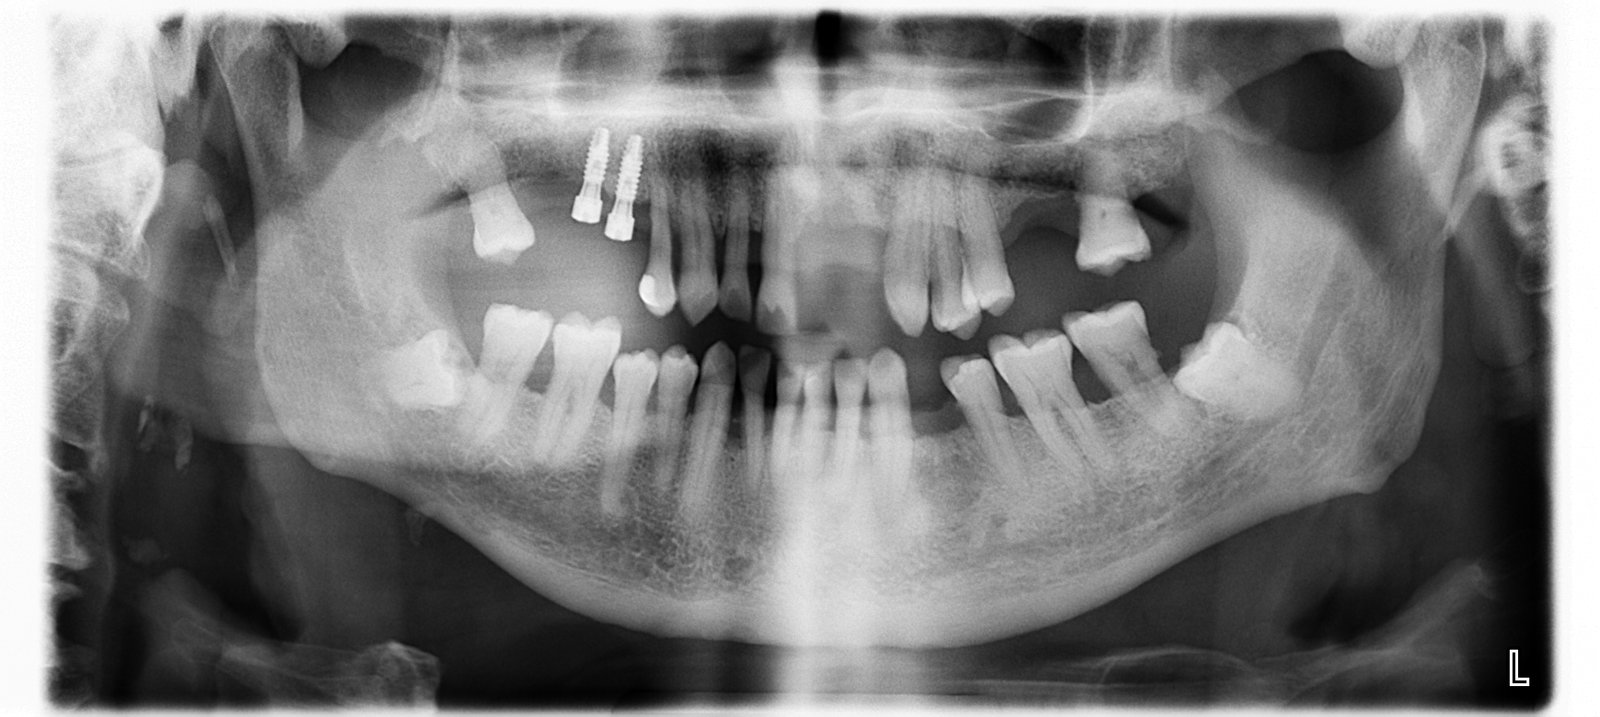

Buenos días compañeros! Me ha llegado una paciente de idental que desconoce la marca y tamaño de los implantes que lleva en boca. Se algunas marcas que usaron en idental [...]

Necesitamos realizar a la paciente una cirugía de periimplantária y no sabemos el tipo de implante que lleva, ya que se lo colocaron hace años en una clínica dental en [...]